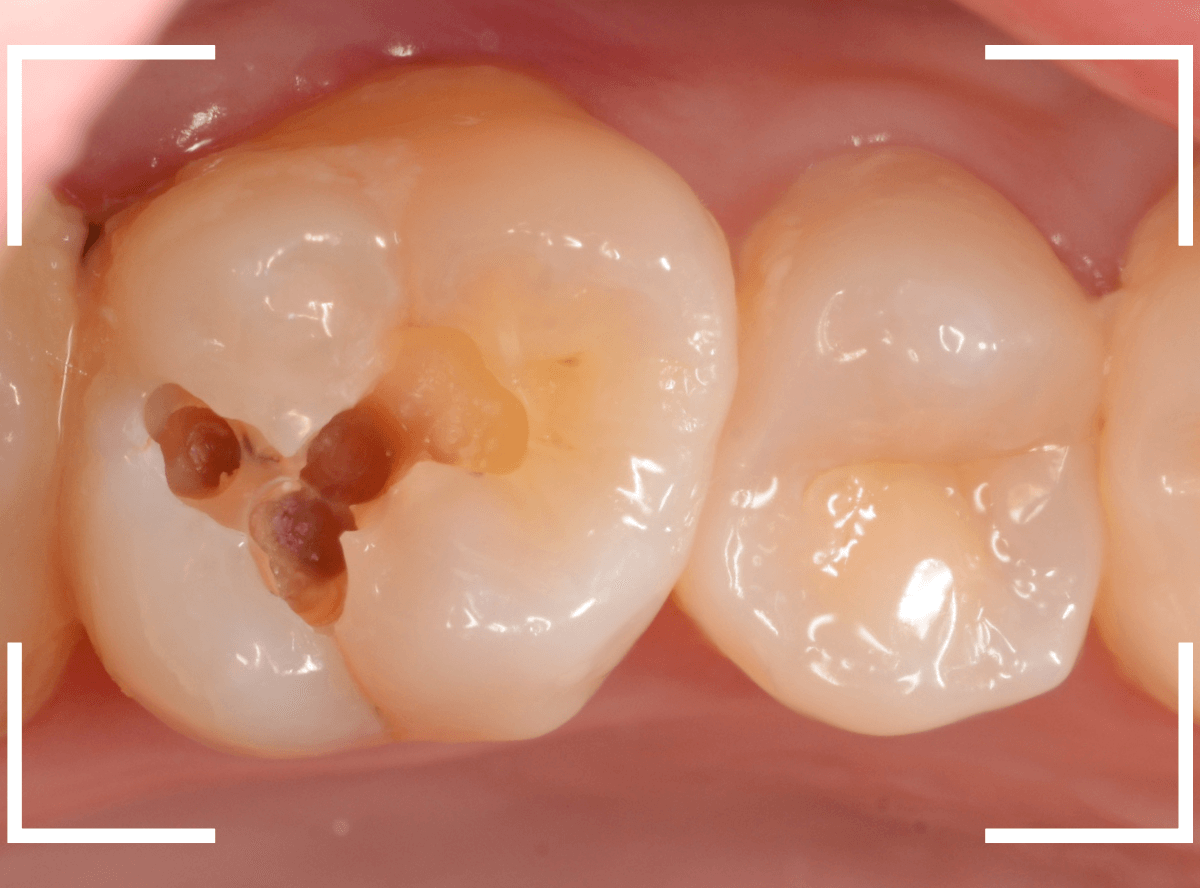

Case.25 深い虫歯の治療~無事にセラミック・インレーへ

今回は、上の奥歯が深くて広い虫歯になっていた方のケースです。

〇部が虫歯の部分です。

この写真からは深い虫歯があるのは想像つきません。

奥歯から治療を開始します。

少し削ると、すぐに虫歯の部分が出てきました。

慎重に虫歯を削っていきます。

レントゲンから想像した通り、かなり大きな虫歯です。

奥の歯の虫歯を全て除去したところです。

やはりかなり深くて広い虫歯でした。